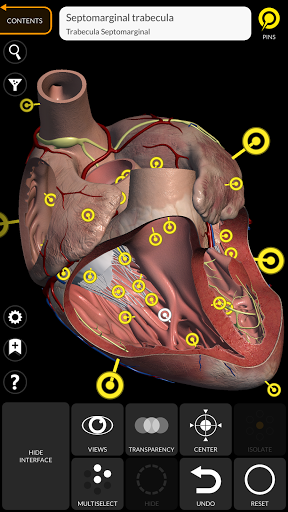

يتيح لك "Anatomy 3D Atlas" دراسة التشريح البشري بطريقة سهلة وتفاعلية.

من خلال واجهة بسيطة وبديهية، من الممكن ملاحظة كل بنية تشريحية من أي زاوية.

تتميز النماذج التشريحية ثلاثية الأبعاد بتفاصيل خاصة ودقة تصل إلى 4K.

• من خلال تحديد نموذج أو دبوس، يظهر المصطلح التشريحي ذي الصلة

• وصف العضلات: الأصل والإدخال والتعصيب والعمل